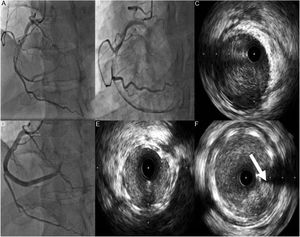

Caso clínico 2Doente do sexo masculino, 53 anos, previamente saudável, praticante regular de desporto, sem fatores de risco cardiovasculares conhecidos, nem antecedentes patológicos ou familiares relevantes e sem medicação crónica. Recorre ao serviço de urgência por dor torácica de características opressivas com início três dias antes da ida ao SU com progressivo aumento de intensidade. À admissão apresentava‐se hemodinamicamente estável, sem alterações relevantes ao exame físico, nomeadamente à auscultação cárdio‐pulmonar. Realizou ECG que mostrava ritmo sinusal 93/min, supradesnivelamento ST na parede anterior e ondas Q patológicas na parede inferior e anterior (Figura 3). O doente foi submetido a cateterismo cardíaco urgente, que revelou disseção coronária espontânea da descendente anterior, na qual, apesar de não ser de todo evidente a presença de um flap, era evidente a presença de hematoma intramural desde o segmento médio, estendendo‐se até ao segmento distal condicionando fluxo TIMI 2 (Figura 3).

A: Eletrocardiograma da admissão. B e C: Coronariografia evidenciando artéria descendente anterior (DA) com disseção espontânea ocupando todo o segmento médio e distal estendendo‐se até ao ramo póstero‐lateral. D: Coronariografia realizada após paragem cardiorrespiratória 30h após admissão, evidenciando aparente progressão proximal da disseção D e F: Imagem de IVUS a evidenciar hematoma intramural desde a DA proximal (seta).

Uma vez que o doente se encontrava hemodinâmica e eletricamente estável, apenas com uma dor residual, e com fluxo coronário TIMI 2, optou‐se por uma estratégia watchfullwaiting, sendo admitido na UCIC para vigilância e monitoração, sob terapêutica antitrombótica tripla com aspirina, clopidogrel e enoxaparina sc em doses terapêuticas.